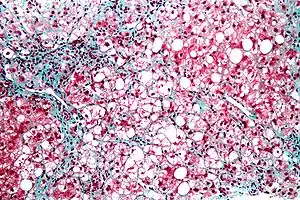

| Micrograph showing a fatty liver (macrovesicular steatosis), as seen in non-alcoholic fatty liver disease. Trichrome stain. | |

The fatty change represents the intracytoplasmatic accumulation of triglycerides (neutral fats). At the beginning, the hepatocytes present small fat vacuoles (liposomes) around the nucleus (microvesicular fatty change). In this stage, liver cells are filled with multiple fat droplets that do not displace the centrally located nucleus. In the late stages, the size of the vacuoles increases, pushing the nucleus to the periphery of the cell, giving a characteristic signet ring appearance (macrovesicular fatty change). These vesicles are well-delineated and optically "empty" because fats dissolve during tissue processing. Large vacuoles may coalesce and produce fatty cysts, which are irreversible lesions. Macrovesicular steatosis is the most common form and is typically associated with alcohol, diabetes, obesity, and corticosteroids. Acute fatty liver of pregnancy and Reye's syndrome are examples of severe liver disease caused by microvesicular fatty change.[19] The diagnosis of steatosis is made when fat in the liver exceeds 5–10% by weight.[13][20][21]